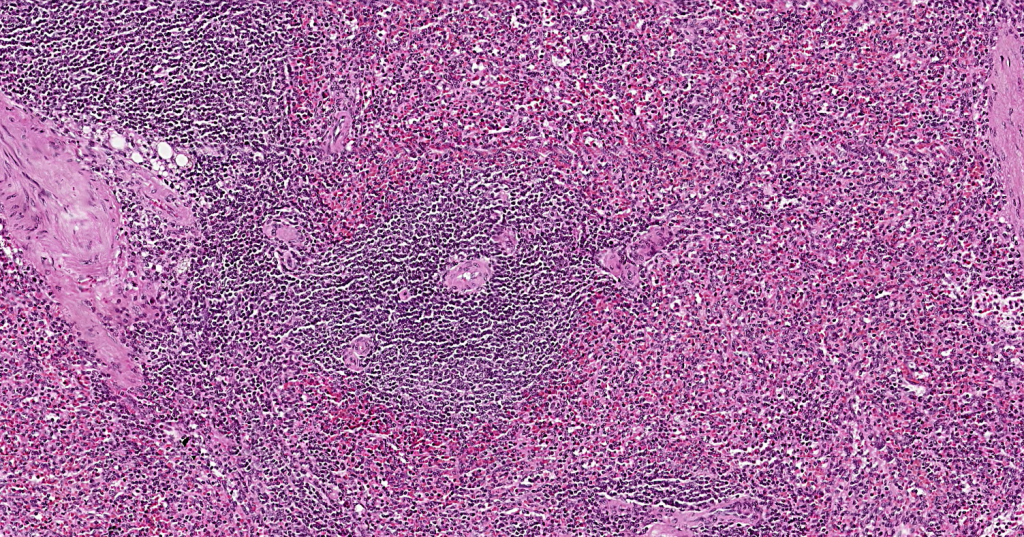

GANGLIOS LINFÁTICOS

Órgano linfoide 2° (secundario)

Se encarga de filtrar la linfa, e iniciar respuestas inmunitarias.

Hay nódulos linfáticos en su corteza.

Los ganglios linfáticos son órganos linfoides arriñonados de 2-20mm de diámetro. La linfa se filtra a través de ellos.Los ganglios son órganos linfoides encapsulados con presencia de nódulos linfáticos en su corteza.Algunas de sus funciones principales son la filtración de linfa antes de devolverla al conducto torácico, la producción de linfocitos que se añaden a la linfa y la recirculación de linfocitos.Observe la cápsula de TCDi y los nódulos linfoides en la corteza.Con impregnaciones argénticas podemos observar fibras reticulares (Colágena III)Identifique.